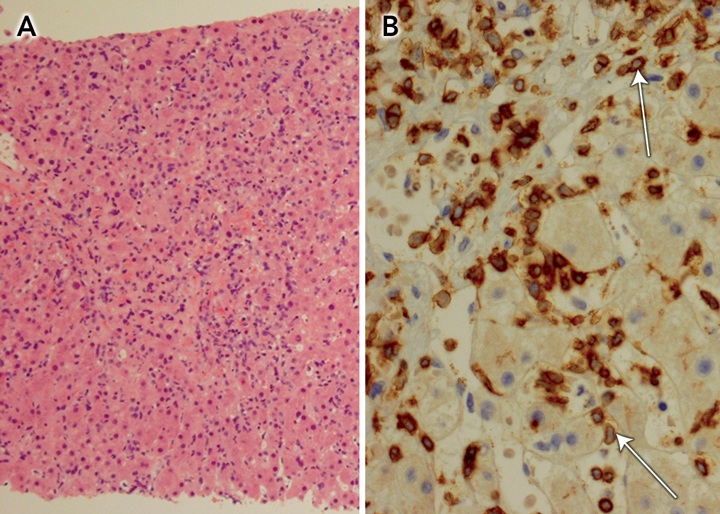

Abdominal computed tomography confirmed gross splenomegaly, with the spleen being 24 cm long on its major axis, but no lymphadenopathy. Microscopic examination of a liver core biopsy specimen revealed an atypical lymphoid infiltrate in the sinusoids, especially around central veins (Box), with immunophenotype bcl-2+, CD3+, CD43+, Ki67+, ALK1 −, bcl-6 − , CD5 −, CD10 −, CD20 −, CD30 −, CD79 − and cyclin D1 − . Subsequent genetic studies of a bone marrow biopsy specimen revealed rearrangement of the T-cell receptor γ-chain gene, consistent with hepatosplenic T-cell lymphoma (HSTCL).